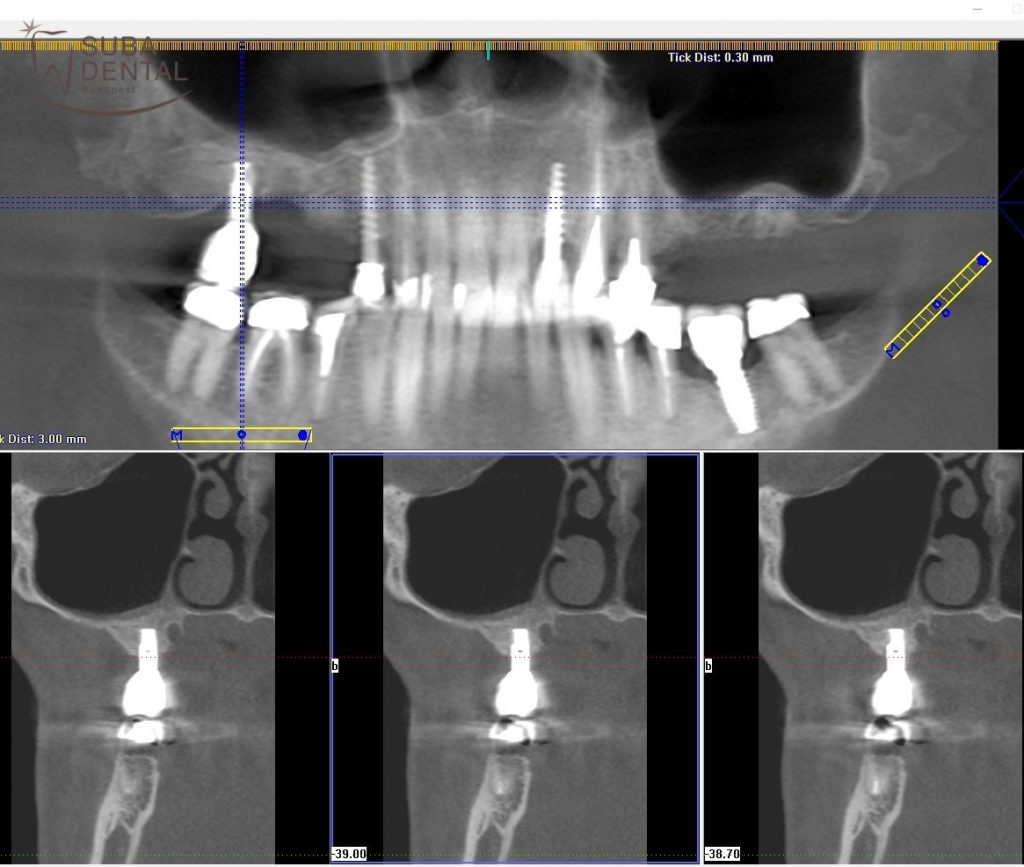

- Amennyiben a régi implantátumok körül gyulladás látszik, periimplantitisre utaló klinikai vagy radiológiai tünetek vannak (vérző, gyulladt íny, fájdalom, csontfelszívódás, genny ürül az implantátum mellől), a fogorvos azonnal kérhet egy 3 dimenziós CBCT röntgenfelvételt. Sajnos az is előfordulhat, hogy nemcsak a koronát, hanem az egész implantátumot el kell távolítani a kezeletlen periimplantitis okozta fertőzés miatt!

A jobb oldali felső utolsó implantátum menthetetlen volt a körülötte kialakult gyulladás és csontveszteség miatt

Bal alsó úgynevezett penge implantátum körül teljesem felszívódott a csont. Sürgősen el kellett távolítani, mivel gennyes, fájdalmas volt

Rendszeres ellenőrzés elmulasztása miatt minden implantátumot el kellett távolítani, mert mindegyik körül úgynevezett periimplantitis alakult ki

Implantátum körüli gyulladás intraorális röntgenfelvételen